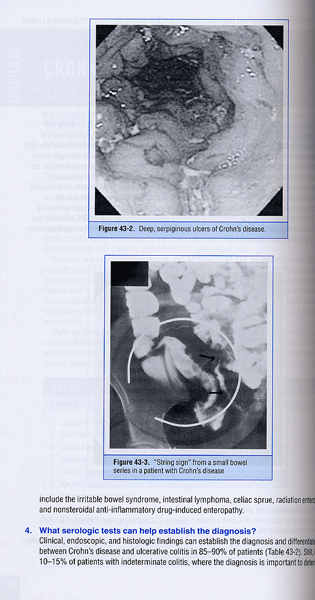

43. Crohn’s Disease